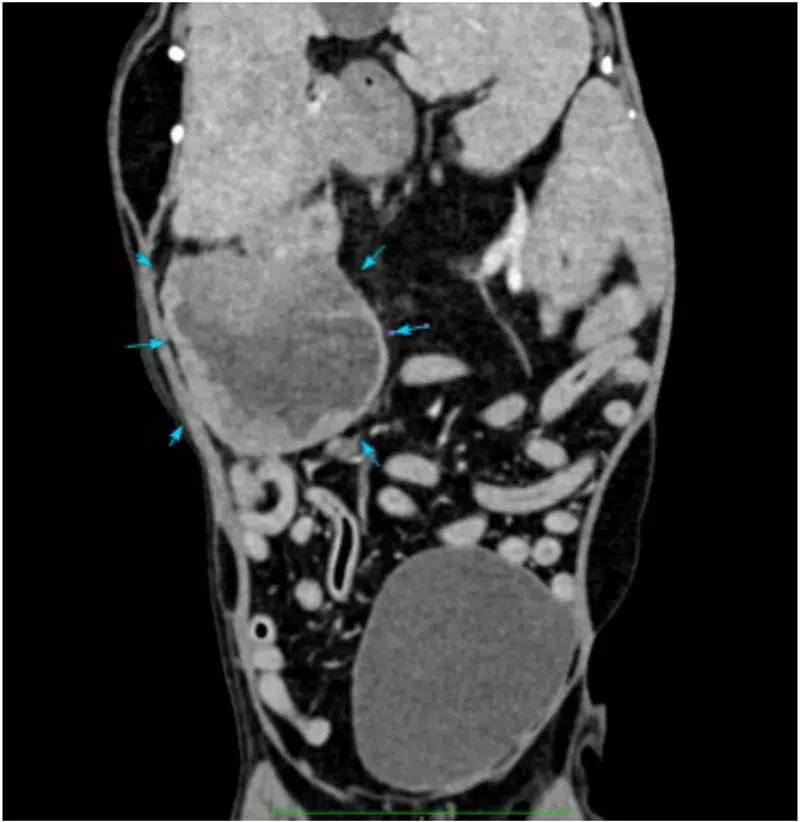

Fluid accumulations

In a minority of dogs with pancreatitis (some acute), pancreatic fluid accumulations can develop (Figure 3)23. These appear to contain neutrophilic inflammation, though the majority have negative bacterial cultures – complicated often by previous administration of antibiotics – so it is unclear how many are septic and how many are a response to severe inflammation.

Medical management can be successful, even leading to resolution, but surgical exploration is ultimately required in some, albeit with a high mortality rate23.